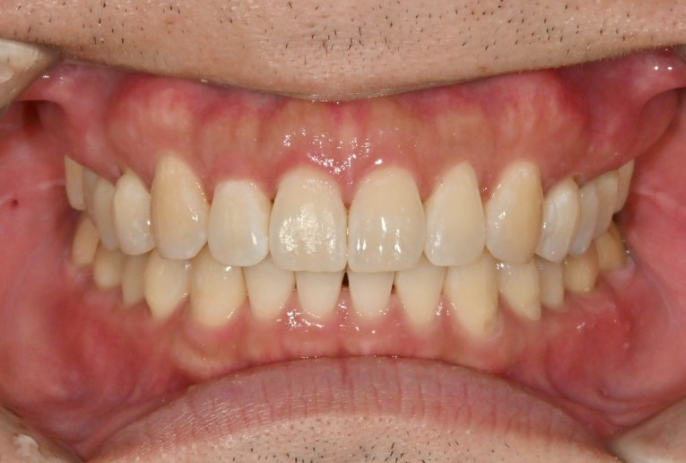

25.10

정확히 일치하는 중심선이 눈에 띕니다.

과개교합은 개선되어 이제 아래 앞니가 절반 이상 보입니다.

어금니 교합은 물샐틈 없는 1급 교합관계를 보입니다.

총 치료기간은 11개월에 재제작 1회 입니다.